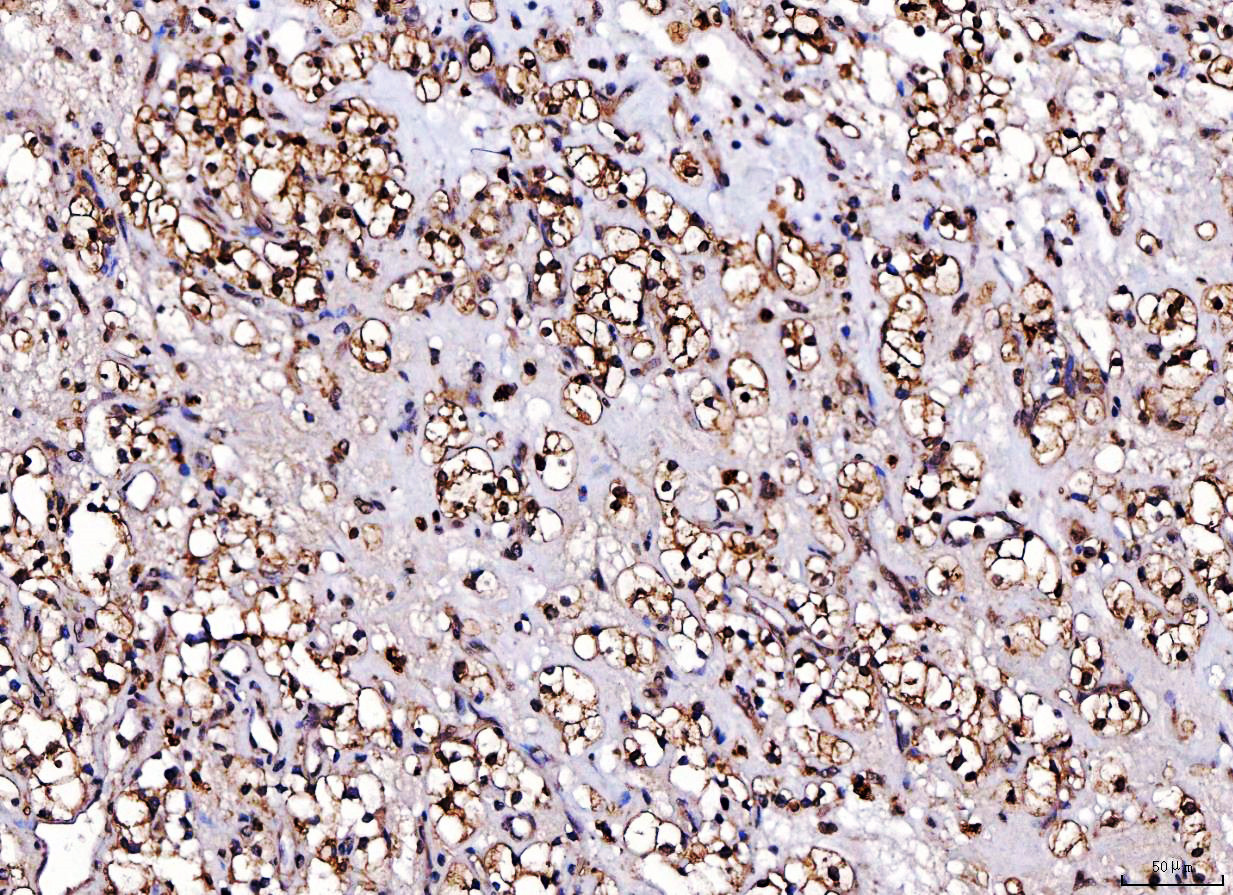

IHC analysis of CDK2 using anti-CDK2 antibody (M00166-4).

CDK2 was detected in a paraffin-embedded section of human liver cancer tissue. Biotinylated goat anti-mouse IgG was used as secondary antibody. The tissue section was incubated with mouse anti-CDK2 Antibody (M00166-4) at a dilution of 1:200 and developed using Strepavidin-Biotin-Complex (SABC) (Catalog # SA1021) with DAB (Catalog # AR1027) as the chromogen.